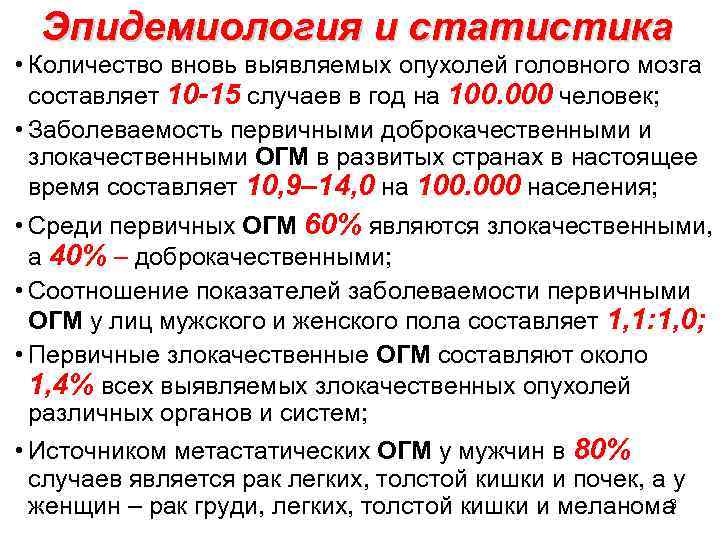

Эпидемиология и статистика • Количество вновь выявляемых опухолей головного мозга составляет 10 -15 случаев в год на 100. 000 человек; • Заболеваемость первичными доброкачественными и злокачественными ОГМ в развитых странах в настоящее время составляет 10, 9– 14, 0 на 100. 000 населения; • Среди первичных ОГМ 60% являются злокачественными, а 40% – доброкачественными; • Соотношение показателей заболеваемости первичными ОГМ у лиц мужского и женского пола составляет 1, 1: 1, 0; • Первичные злокачественные ОГМ составляют около 1, 4% всех выявляемых злокачественных опухолей различных органов и систем; • Источником метастатических ОГМ у мужчин в 80% случаев является рак легких, толстой кишки и почек, а у 3 женщин – рак груди, легких, толстой кишки и меланома